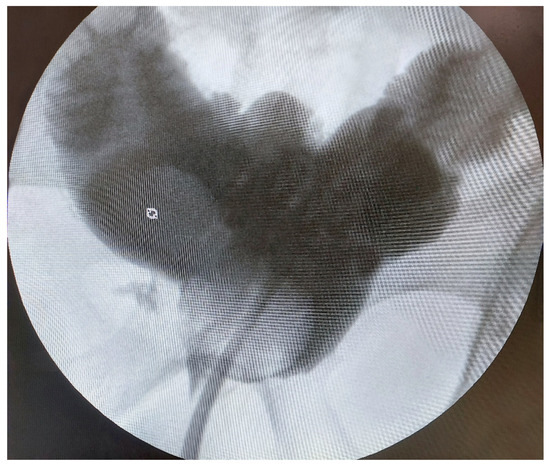

- A Vicryl 3/0 suture is used to approach the posterior periurethral tissue, the Denonvillier fascia, and the posterior margin of the neobladder neck, similarly to Rocco’s stitch used in radical prostatectomy. Finally, neobladder-urethral anastomosis is performed on a Foley 18F or 20F catheter with two continuous Vicryl 3/0 sutures (Figure 3D). The neobladder is then slowly filled with 100–150 mL of saline to confirm water tightness.